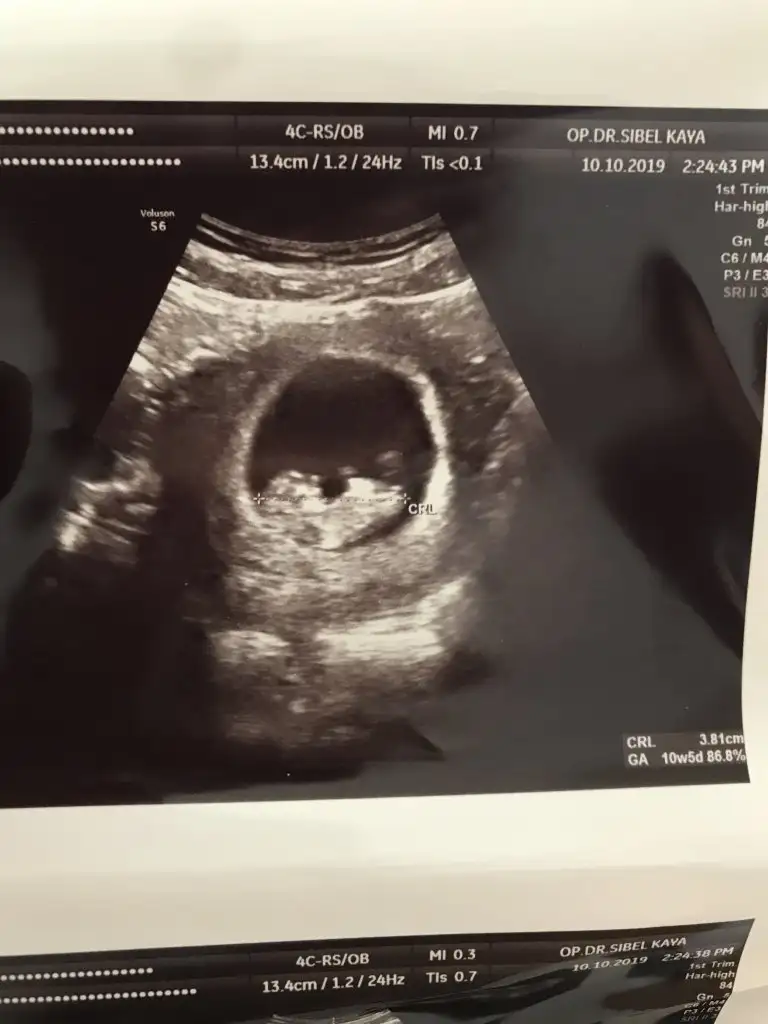

Kız gibi tam net degil 12 hafta usg de paylaşın bir dakineİyi pazarlarbende bir tahmin alabilir miyim acaba ? 10 hafta 5 günlük usg görüntüsü eklediğim.

Kiz gibi net degilİyi pazarlarbende bir tahmin alabilir miyim acaba ? 10 hafta 5 günlük usg görüntüsü eklediğim.